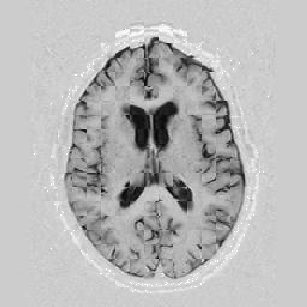

Lastly, Figure [*] shows 10 iterations at level 2, 6 iterations at level 1, and 6 at level 0.

Figure: Multi-scale NRR. From left to right, top then bottom: before NRR; after 10 iterations of NRR at level 2; after another 6 iterations of NRR at level 1; after 6 more iterations at level 0.